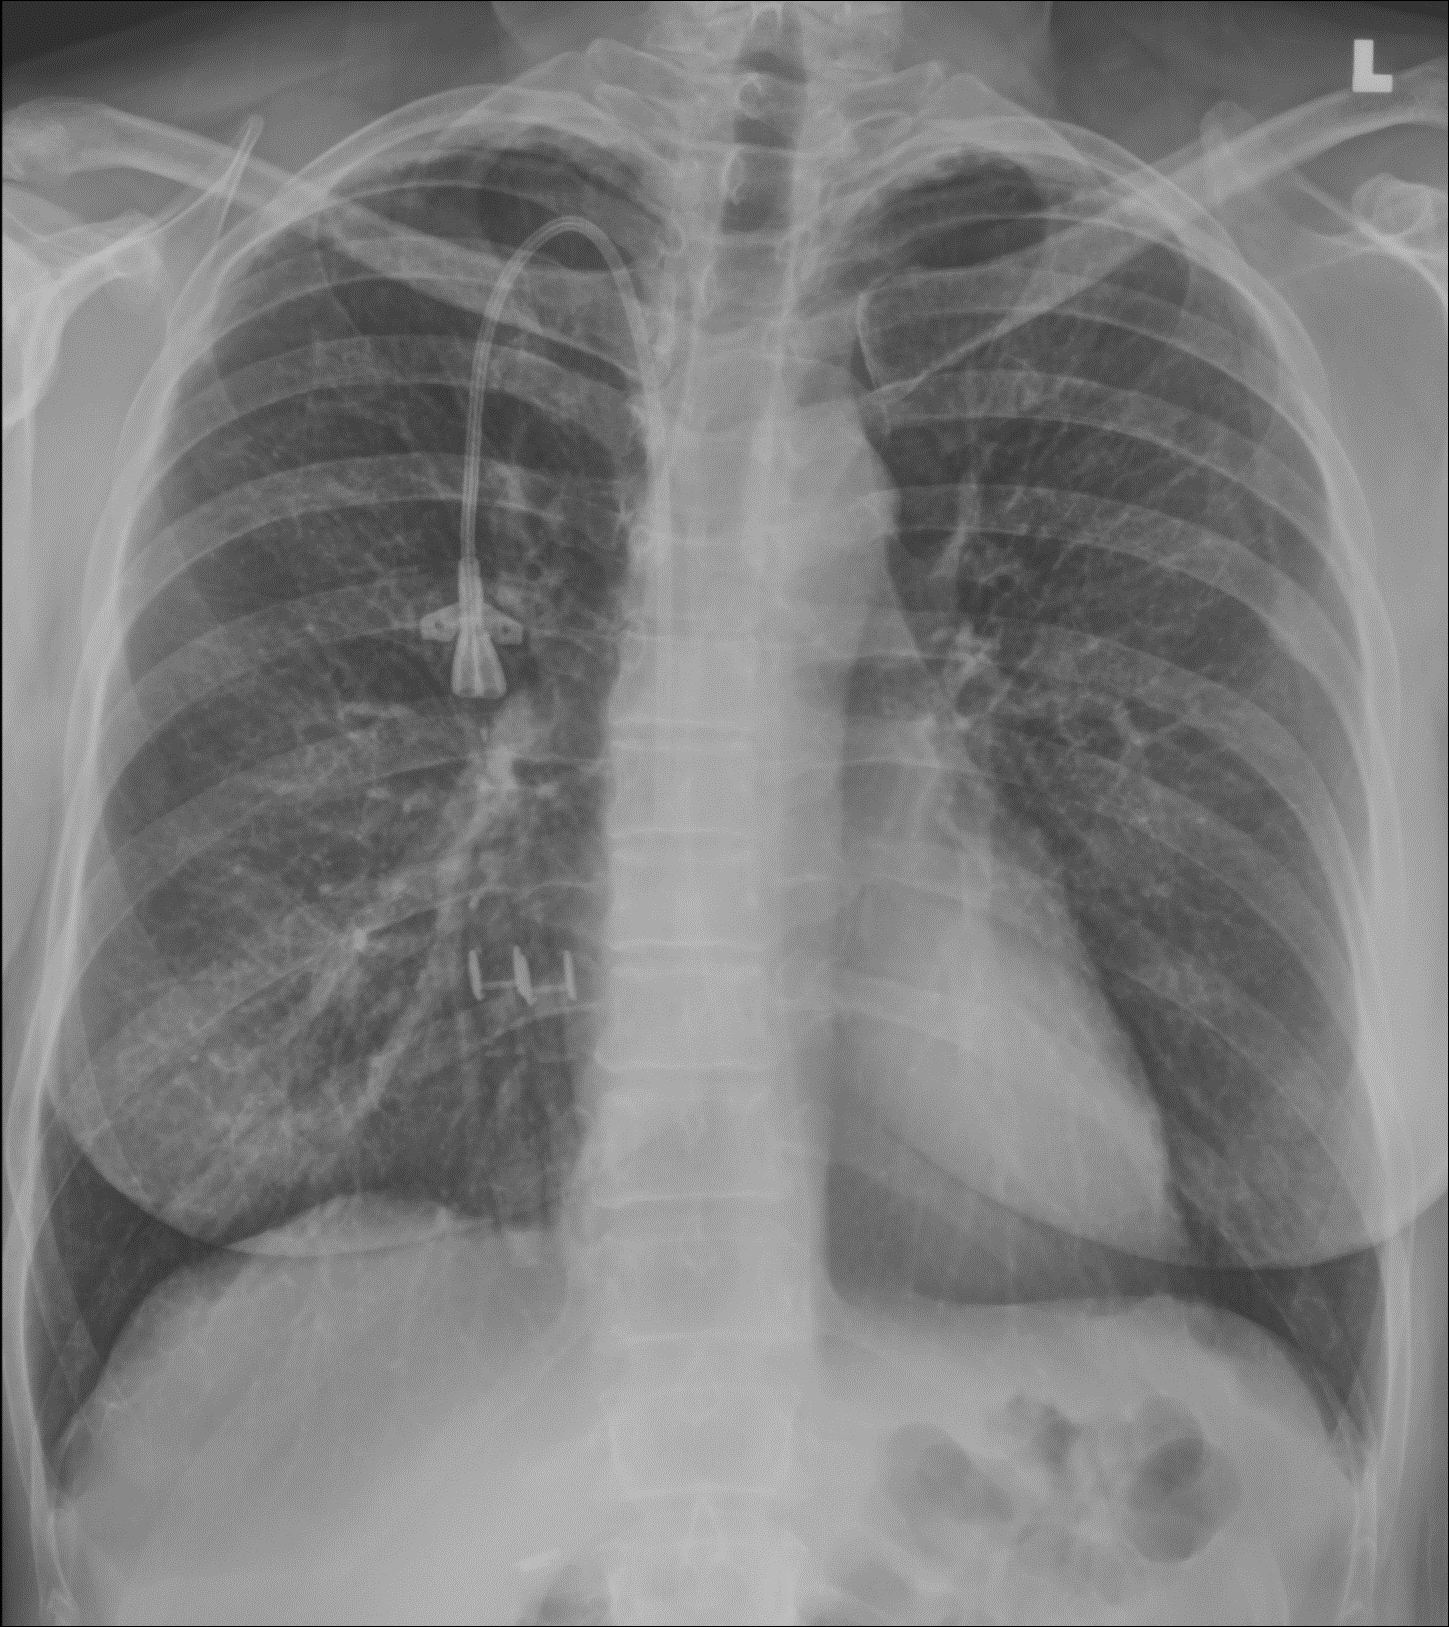

Dual-energy images from the Reveal™ detector helped find lung nodules and scarring that were hard to pick up on the X-ray image. The dual-energy images also showed positioning of lines and tubes very clearly, which can be difficult to appreciate on portable X-ray images.

These images allow clinicians to separate overlapping anatomical structures and visualize areas that may be less visible in conventional radiographs.

Unlike traditional dual-energy imaging techniques that require multiple exposures, SpectralDR captures these images simultaneously with a single exposure, eliminating motion artifacts and maintaining the same clinical workflow as standard portable radiography.